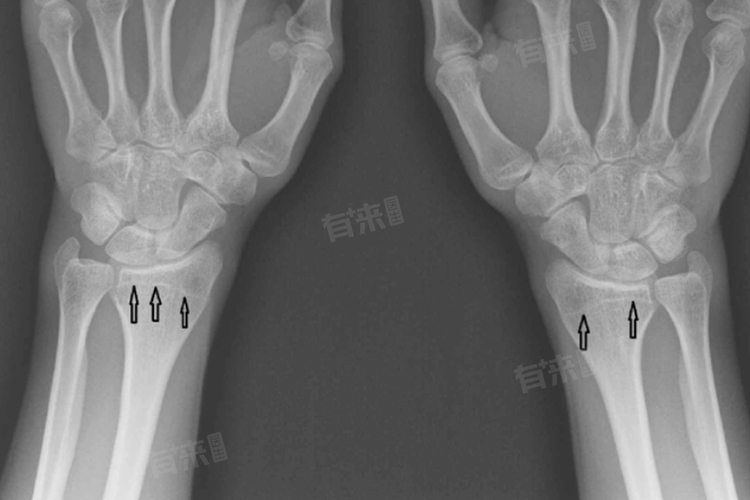

- 骨骼线即骨骺线或生长板,是儿童和青少年时期长骨两端之间的软骨区域,这一区域富含活跃的细胞,负责骨骼的增长与扩展,直到青春期结束时逐渐钙化并最终闭合,标志着骨骼生长的完成。